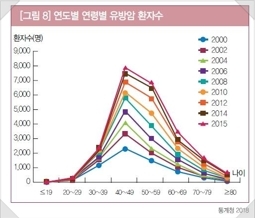

• 국가암 통계 결과, 우리나라 유방암은 30~40대의 젊은 연령층의 여성들에게도 많이 발생하고 있습니다.

• 심지어 20대 젊은 연령대에서도 빈도는 적지만 약 10% 미만에서 진단이 되고 있습니다.